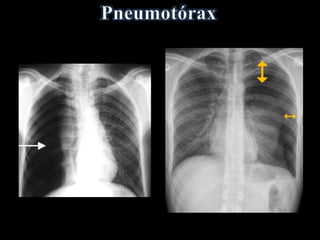

• Ar livre na cavidade pleural

• Faixa de ar (hiperlúcida) entre a pleura

visceral e:

a parede torácica e/ou diafragma

• Desvio de mediastino contralateralmente

• Acentuado na Expiração Forçada